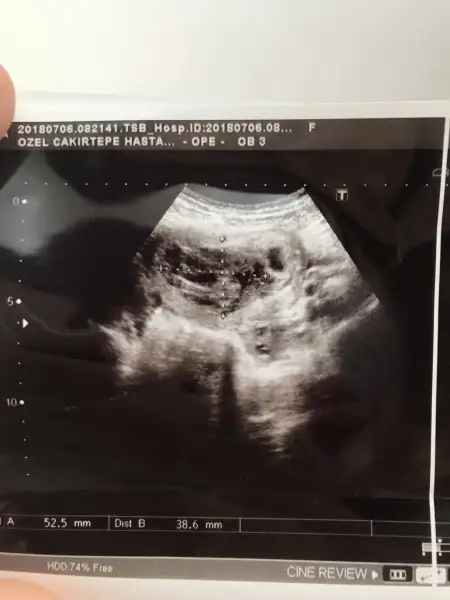

Kızlar doktorun işaretlerini yer kanama bölgem yan tarafta yuvarlak yer ise bebeğin bulunduğu kese

Eklentiler

• image.webp

12,8 KB · Görüntüleme: 91